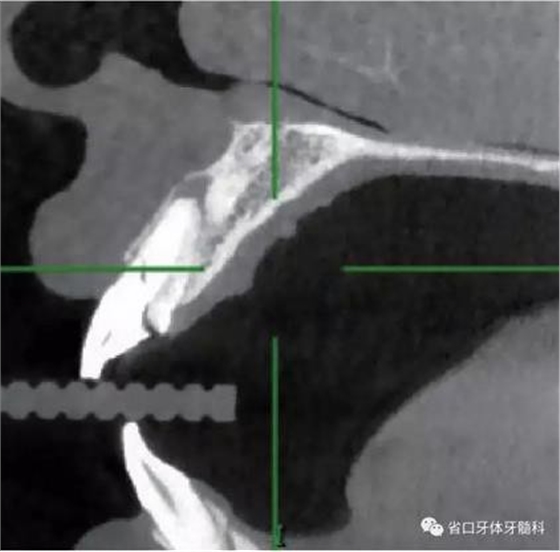

1.?病例簡介 43歲女性患者,主拆:右上前牙松動不適數(shù)日要求修復(fù)。現(xiàn)病史:患者數(shù)年前右上前牙因“齲壞”于外院行根管治療(具體不詳),數(shù)日前牙冠松動不適,現(xiàn)覺影響咀嚼及美觀,遂來我院要求進(jìn)一步診治。否認(rèn)高血壓、心臟病等重大疾病,否認(rèn)結(jié)核、肝炎等傳染病史,否認(rèn)手 術(shù)、輸血史等,未發(fā)現(xiàn)藥物過敏。無吸煙習(xí)慣。臨床檢查:口外觀顏面基 本對稱,皮膚無紅腫破潰,顳下頜關(guān)節(jié)區(qū)無彈響、雜音、壓痛,開口度約 37mm,開口型“↓”,頜下、刻下和頸部未及腫大淋巴結(jié)。中位笑線??趦?nèi)檢查,口腔衛(wèi)生可,色素(+),BOP(-),PD=2mm,上頜右側(cè)中切 牙冠部變色,冠根折斷至齦下3mm,叩不適,松動Ⅱ°~Ⅲ°。牙齦稍紅, 齦緣水平及齦乳頭高度可,屬于中厚齦生物型,附著齦寬度約5mm,唇系帶附著可。上頜右側(cè)中切牙缺牙間隙與對側(cè)同名牙一致,約>7mm,修復(fù)空 間良好。與對頜牙覆合覆蓋正常。MCT檢查示上頜右側(cè)中切牙冠根折斷至骨 下,根管內(nèi)見充填物,根充不全,根尖見陰影,大小約3mm×3mm。牙槽窩根方可用骨量可,唇側(cè)骨壁完整,冠方骨壁厚度約1mm。

(1)微創(chuàng)拔牙及即刻種植:術(shù)前拍攝口內(nèi)照及實(shí)施牙周基礎(chǔ)治療。常 規(guī)消毒鋪巾阿替卡因局麻下微創(chuàng)拔除上頜右側(cè)中切牙,搔刮拔牙窩及根尖肉 芽組織。探測牙槽骨唇側(cè)骨壁及鄰面牙槽嵴完整,牙齦無撕裂。不翻瓣下于上頜右側(cè)中切牙缺隙近遠(yuǎn)中中點(diǎn)的腭側(cè)牙槽骨及根方定位,按照逐級預(yù)備的原則,緊貼牙槽窩腭側(cè)骨壁制備種植窩洞,植入Zimer®3.7mm×13mm TSV種植體1顆,植入扭矩>35N·cm,以O(shè)sstell測量種植體的ISQ值為68。 種植體平臺位于唇側(cè)齦緣中點(diǎn)下3mm,與唇側(cè)骨壁內(nèi)側(cè)面形成的跳躍間 隙約2mm,置入Bio-Oss®細(xì)顆粒骨粉0.25g,上愈合基臺關(guān)閉創(chuàng)口。術(shù)后 CBCT檢查顯示:種植體利用牙槽窩根方骨質(zhì)固位,緊貼牙槽窩腭側(cè)骨壁, 其唇側(cè)面與牙槽窩唇側(cè)骨壁的內(nèi)側(cè)面所形成的跳躍間隙(約2mm)可見顆 粒狀顯影物充填。牙槽窩的唇側(cè)骨壁及唇側(cè)倒凹無缺損穿孔。

圖4 術(shù)前X線片

圖19 術(shù)后MCT